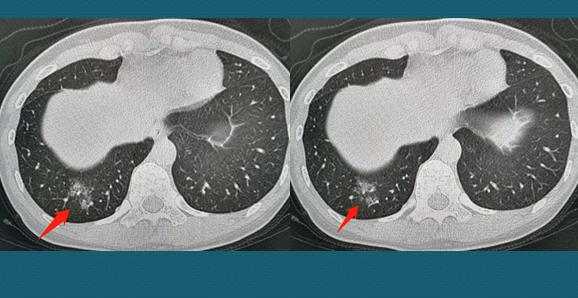

这位年轻的女士因为受凉后出现咳嗽、少量白色痰、发热,体温最高38℃,CT查出右下肺少量淡片状影,瞬间紧张起来:

跟前面那位女士一样,她没有疫区生活史,没有接触从疫区过来的人群,相关的化验检查也不支持病毒性感染。抗炎治疗后体温恢复正常,咳嗽明显减轻,一周后复查CT明显吸收: